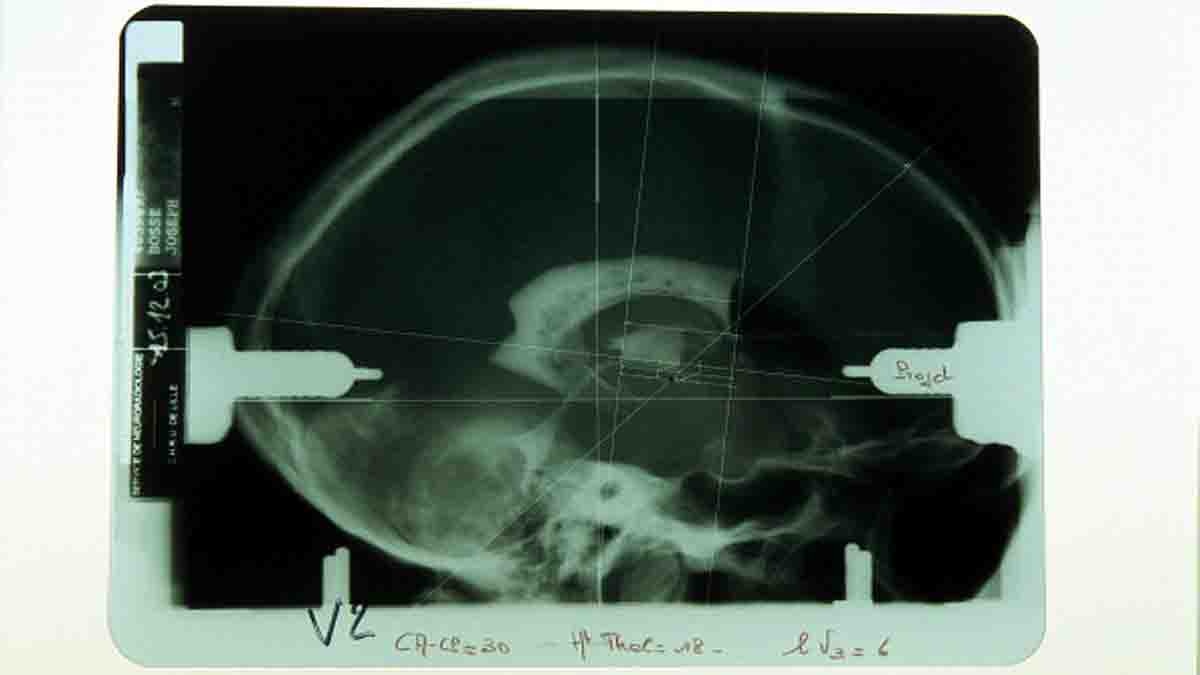

स्पेन के वैज्ञानिकों ने दृष्टिहीन लोगों को देखने के लिए नई तकनीक ईजाद की है. इस तकनीक में मरीज के दिमाग में खास तरह का इम्प्लांट लगाया जाता है, जिससे वो बिना दृष्टि के ही देख सकता है. वैज्ञानिक इस तकनीक के जरिए दिमाग के विजुअल कॉरटेक्स को सक्रिय कर देते हैं. जिससे उसके दिमाग में सामने दिखने वाली चीजें स्पष्ट तौर पर तस्वीर बनने लगती है. (फोटोः गेटी)

स्पेन के वैज्ञानिकों ने एक चश्मा बनाया, जिसके बीच में आर्टिफिशियल रेटिना (Artificial Retina) लगा है. यह रेटिना दिमाग में लगे इम्प्लांट से जुड़ा होता है. जैसे ही रोशनी इस रेटिना पर पड़ती है वह इलेक्ट्रिक्ल सिग्नल इम्प्लांट पर भेजता है. यह इम्प्लांट उस रोशनी का एनालिसिस करके दिमाग के विजुअल कॉरटेक्स में रेटिना के सामने दिख रही चीजों की तस्वीर बना देता है. (फोटोः गेटी)

शोधकर्ताओं ने इस चश्मे और इम्प्लांट का परीक्षण 57 वर्षीय महिला पर किया, जो पिछले 16 सालों से कुछ भी नहीं देख पा रही थी. वह पूरी तरह से दृष्टिहीन थीं. ब्रेन में इम्प्लांट लगने के बाद जैसे ही महिला ने आर्टिफिशियल रेटिना वाले चश्में को आंखों पर लगाया, उनके सामने दिखने वाली चीजों की इमेज उनके दिमाग में बनने लगी. उन्होंने यह भी बताया कि उनके सामने किस तरह की चीजें रखी हैं. (फोटोः गेटी)

द जर्नल ऑफ क्लीनिकल इन्वेस्टिगेशन में प्रकाशित इस स्टडी में वैज्ञानिकों ने बताया है कि इस तकनीक की मदद से हम दिमाग के उन न्यूरॉन्स को सक्रिय कर देते हैं, जिनसे दिमाग में आर्टिफिशियल रेटिना के सामने दिख रही चीजों की बाहरी आकृति दिखने लगती है. यानी आकार स्पष्ट हो जाता है. (फोटोः गेटी)

दिमाग में लगाया गया इम्प्लांट सिर्फ 4 मिलीमीटर चौड़ा था. इसके अंदर लगे माइक्रोइलेक्ट्रोड 1.5 मिलीमीटर लंबे थे. यह दिमाग में इस तरह से लगाए जाते हैं कि यह विजुअल कॉरटेक्स में होने वाले इलेक्ट्रिकल एक्टिविटी को सक्रिय कर सकें. साथ ही उस हिस्से में हो रहे इलेक्ट्रिकल बहाव की निगरानी भी कर सकें. (फोटोः गेटी)